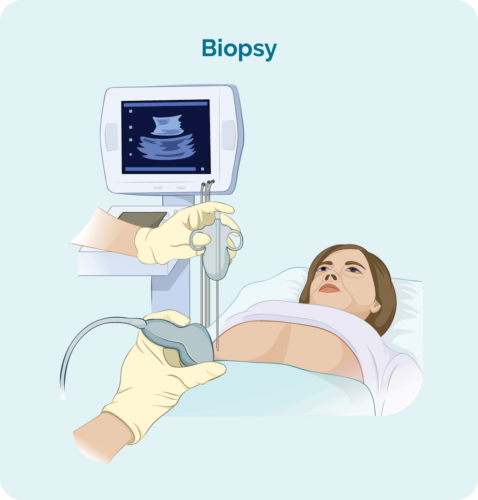

The following day, 22nd May 2025, Travis and his mother met with his GP. It was then that he learned about the mass growing in his chest: “It was explained that it was indicative and highly probable to be Lymphoma or some other form of cancer.” That same day, Travis was supported and triaged through the emergency department at Box Hill Hospital and the following day admitted into the cancer ward where a biopsy confirmed Classical Hodgkin Lymphoma Stage 2b. Travis remained at the ward for 2 weeks. The size of his ‘bulky disease’ was 14cm x 8cm x 6cm.